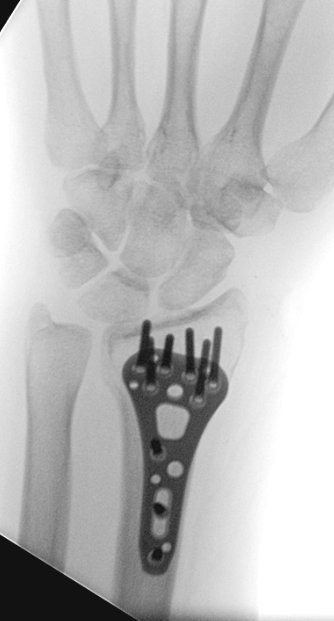

Given the dominant-sided injury, radial and intemediate column injury, joint diastasis, possible SL injury, patient's age, we discussed surgery.

We decided that there was no better way to identify the SL injury other than with our eyeballs. So, scope/fix bone/address ligament.

Scope assisted reduction of the articular surface was pretty cool, but radiographs honestly showed the same story

Ordinarily, I’d change that long/distal screw out, but since I was scoping the joint and didn’t see penetration, I felt ok leaving it

Debrided and pinned the SL